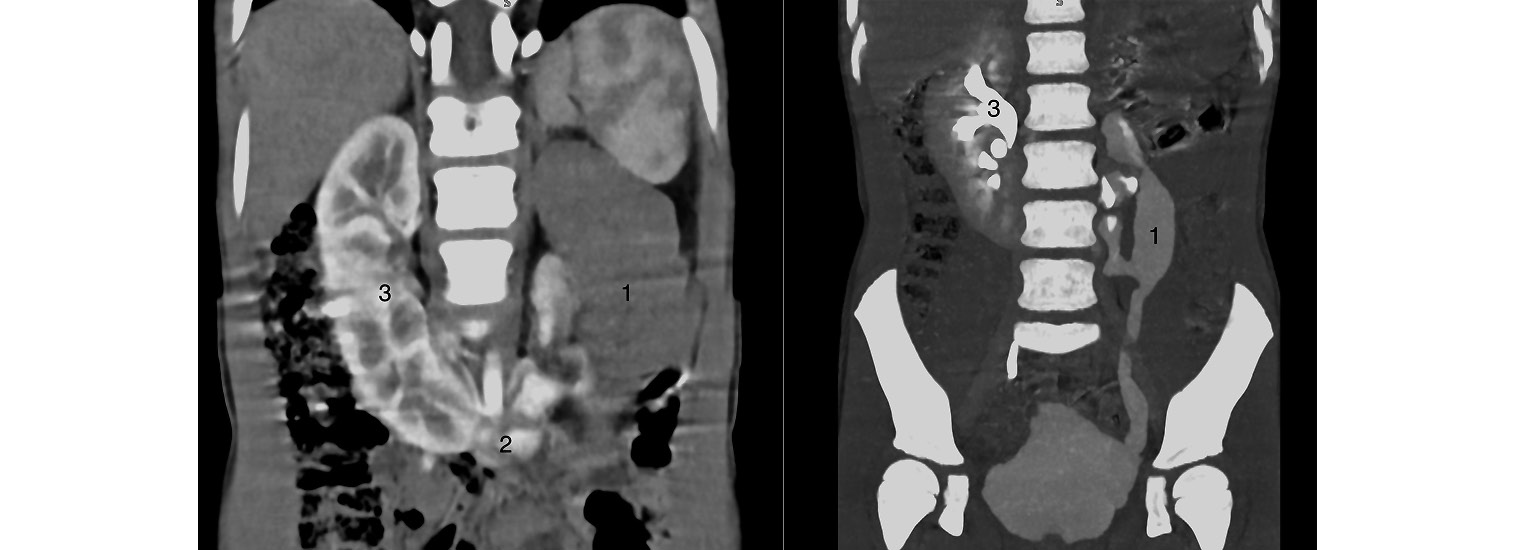

Пациент — мальчик 5 лет с диагнозом «Подковообразная почка с афункциональной левой половиной». Диагноз установлен при помощи ультразвукового исследования (УЗИ), допплеровского исследования почек, контрастной мультиспиральной компьютерной урографии и микционной цистографии, которые позволили определить везикоренальный рефлюкс как причину атрофии левой половины почечной паренхимы (рис. 1).

Рис. 1. Компьютерная томография подковообразной почки с уретерогидронефрозом и потерей функции левой половины: 1 — левая половина подковообразной почки, 2 — перешеек подковообразной почки, 3 — правая половина подковообразной почки.